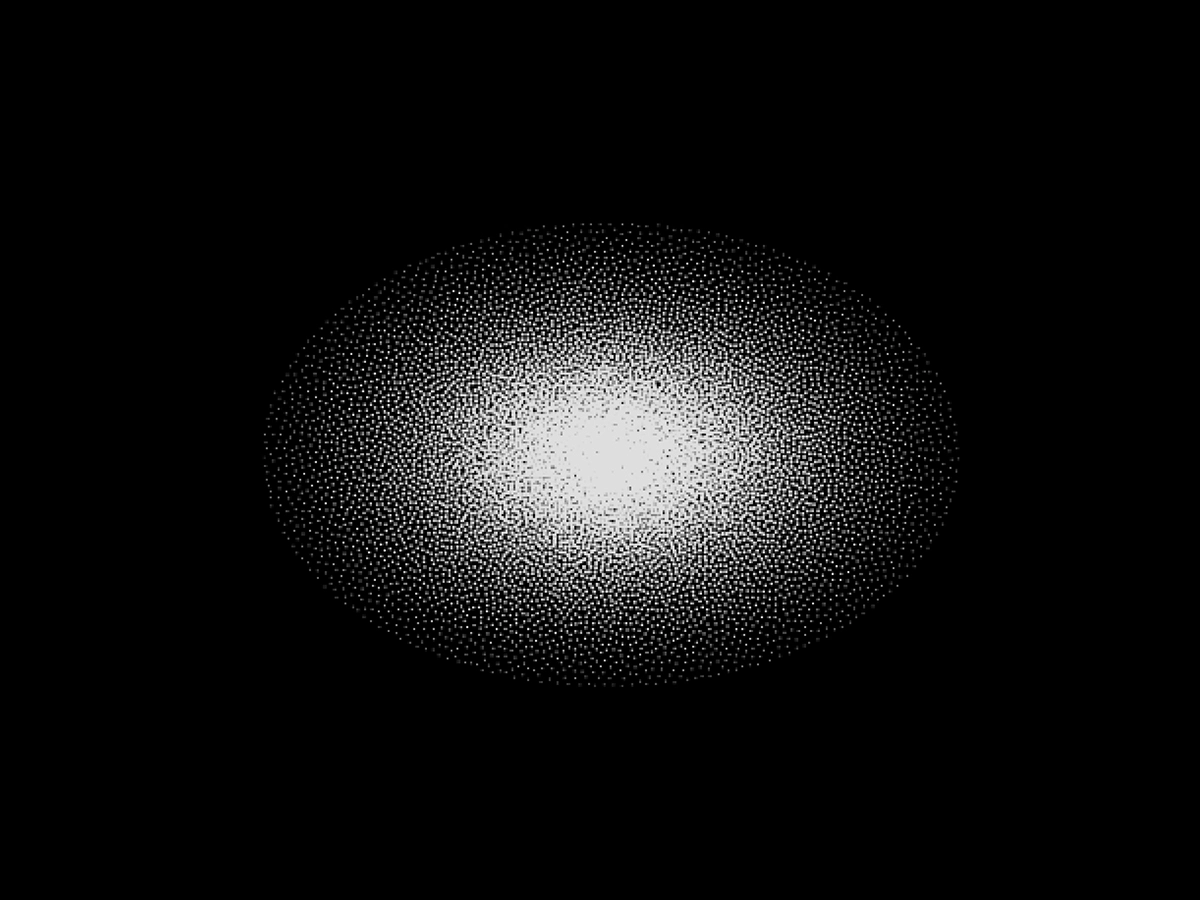

Elliptical K Space

Special K Space filling based on the acquisition only of the encodings in the 2D-3D plane belonging to the ellipse inscribed into the rectangle related to the standard K Space.

Simply said, the corners of the K Space attribute little to the overall image quality so “cutting corners” will reduce the data to be acquired (faster) without compromising quality.

Main characteristics:

- Reduced scan time due the smaller K Space dataset acquisition.

- Available with both 2D and 3D acquisitions.

- Compatible with SpeedUp technique.

- Can be manually enabled and disabled depending on the user preference.